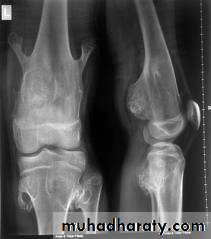

In rickets the changes are maximal where bone growth is occurring , so they are best seen at the knee, wrist and ankle .seen as

. Deficient the zone of provisional calcification .

.widening with irregularly mineralized metaphyses with cupping

.increase distance between the visible epiphysis & the calcified portion of the metaphysis .

.generalized decrease in bone density .

. Deformities of the bones occur because the under mineralized bone is soft , green stick fractures are common .